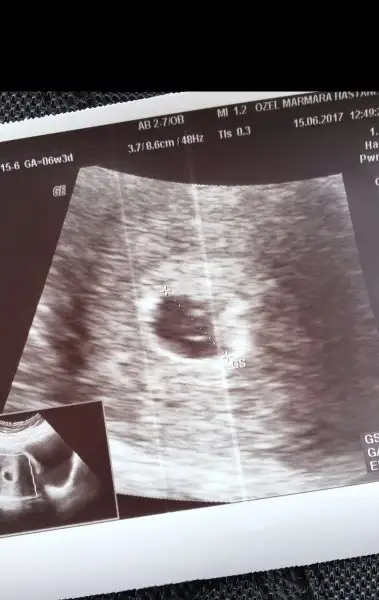

Selam kızlar , kuzenimin 8 haftalık bebeği için cinsiyet tahmini rica ederim . Karından ultrason

Eklentiler

• IMG_2311.webp

IMG_2311.webp

9,7 KB · Görüntüleme: 322

• IMG_2312.webp

IMG_2312.webp

7,8 KB · Görüntüleme: 176